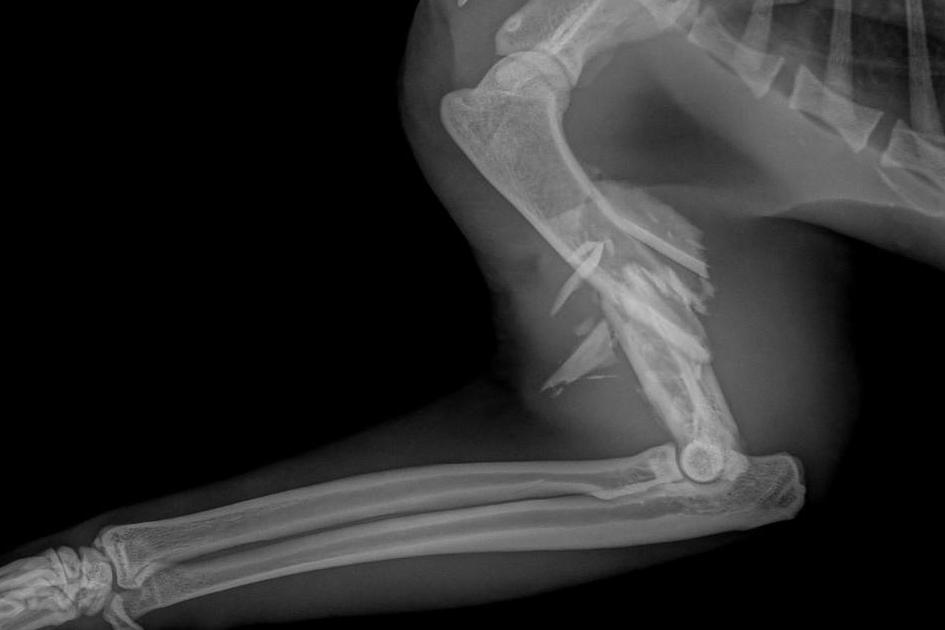

Sweet Pickles came into our care after being found by a member of a public. The vet hospital that assessed him initially found that he was in pain from a broken right arm. Due to the high impact required to cause such a horrible fracture, we suspect that he was hit by a car. Based on the radiographs, the fracture appears irreparable, and thus the recommendation from the vet at this time is to undergo orthopaedic surgery to amputate the leg.